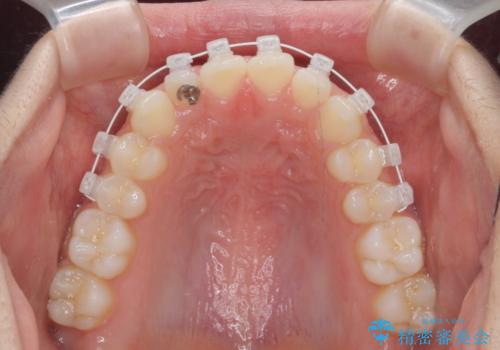

- 矯正装置

- インビザライン

マウスピース矯正インビザラインによる矯正治療を計画しますが、マウスピース矯正で治りにくい歯のねじれを事前にワイヤー矯正でしっかりとなおしておくことで矯正治療期間の短縮できるような治療計画を立てます。

マウスピース矯正を始める前にワイヤー部分矯正を行ったことで改善のしにくい歯のねじれをしっかりと治すことができました。